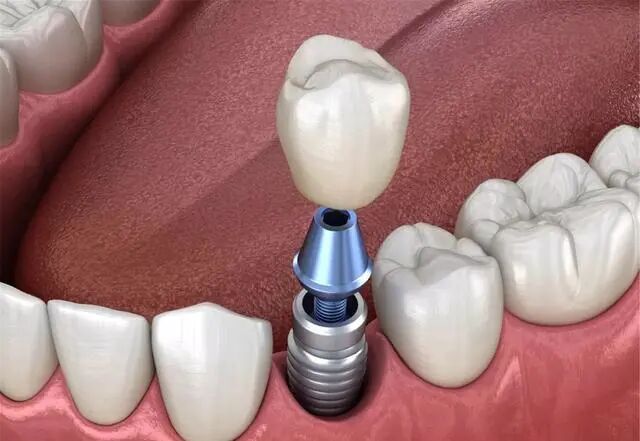

一般种植牙分为三个部分:种植体+基台+牙冠。

如果把我们的牙齿比做一棵树,那么种植体就是树的根基,基台就是树干,牙冠就相当于树枝和树叶。